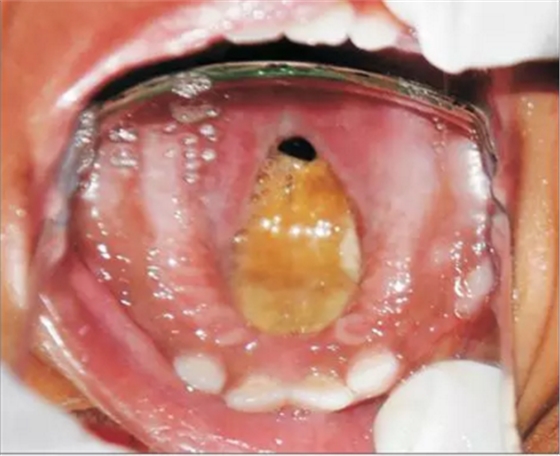

患者為18個(gè)月齡的幼兒,主訴為口腔上腭大面積潰瘍伴鼻腔反流及口腔異味?;純?個(gè)月前曾在外院治療過(guò)肺炎,治療過(guò)后一個(gè)月,患兒家長(zhǎng)發(fā)現(xiàn)患兒上腭出現(xiàn)一小潰瘍并再一次就診。潰瘍?cè)谌靸?nèi)顯著增大并導(dǎo)致上腭穿孔?;純撼霈F(xiàn)吞咽困難及鼻腔反流等癥狀。為求治療穿孔及相關(guān)癥狀及預(yù)防吸入性肺炎來(lái)我院就診。患兒沒(méi)有糖尿病、惡性血液病等病史,也沒(méi)有鼻竇炎或流涕等癥狀。口內(nèi)檢查發(fā)現(xiàn)上腭一暴露骨面的巨大潰瘍,范圍從腭中縫至軟腭,局部穿孔?;純嚎诘?、舌、頰粘膜、唇、鼻中隔皆正常,上頜乳切牙、乳側(cè)切牙、左下頜第一乳磨牙已萌出。

口內(nèi)咬合片可見(jiàn)上頜3×4cm大小低密度影,上頜中切牙恒牙胚移位。